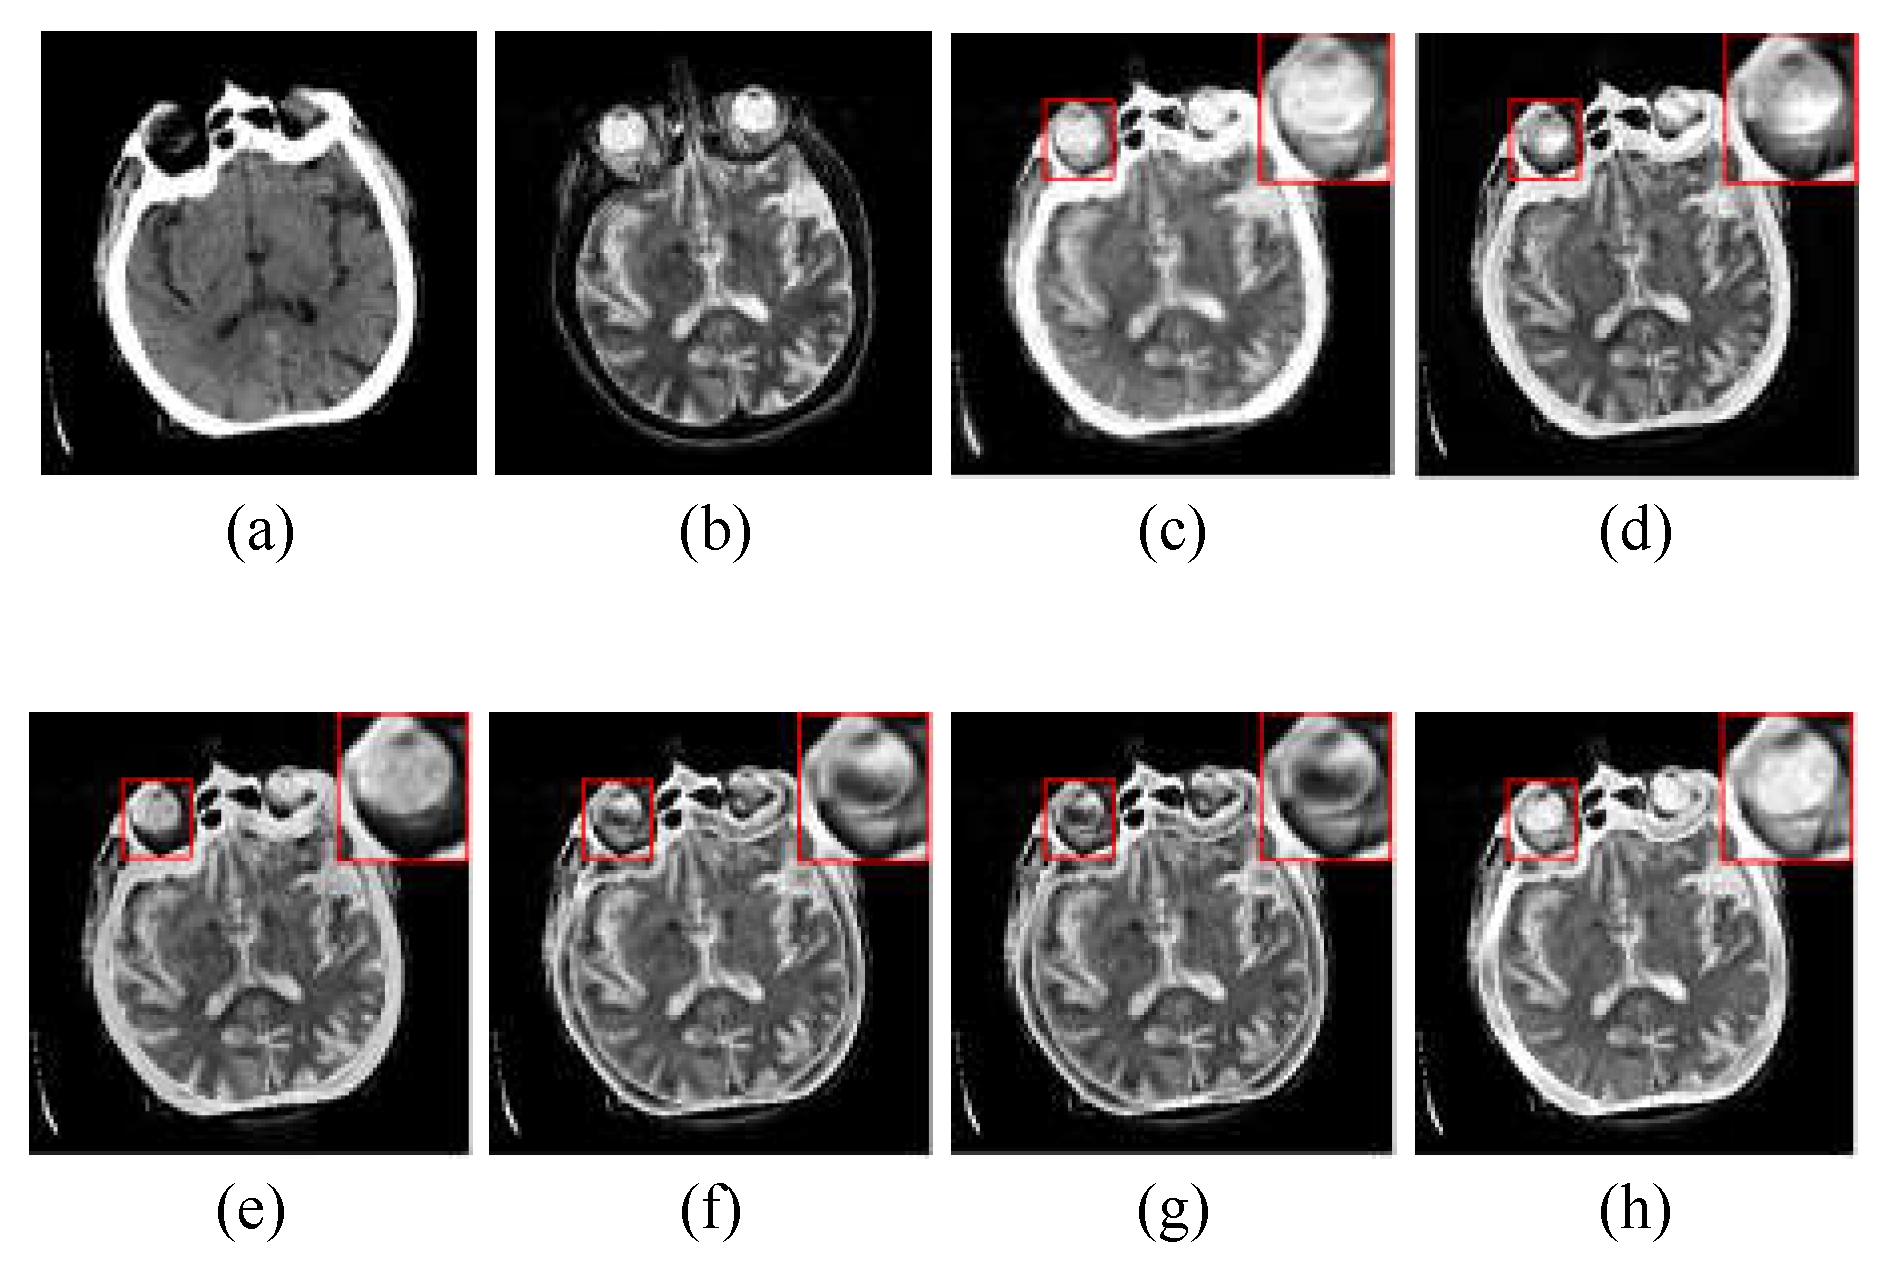

In the experiments of multimodal medical image fusion, CT and MRI image fusion is the most common, since the information provided by CT and MRI images can create a good supplement, while the multimodal combination category can be expanded to other types with the fusion method of this paper. Figure 4 shows the randomly selected nine groups of multimodal medical fused image in subjective visual experiments, and the first three groups belongs to “Acute stroke”, the second three groups belongs to “Hypertensive encephalopathy”, and the last three groups belongs to “Multiple embolic infarctions”. To better intuitively reflect the superiority of the proposed method, one group of typical fusion example is selected from each of the three WBAMI categories to conduct a detail analysis of the amplification of representative regions, as shown in Figure 5,Figure 6Figure 7, respectively.

The CT/MR-T2 fusion results and the red box selections of the proposed method and competitors are shown in Figure 5. The fusion results of LRD and NSST-MSMG-PCNN are blurred since artificial interference is unsuppressed (see (c) and (d) in Figure 5), while CSMCA, l1-norm, SSSF and Proposed as SR-based methods are robust to artificial interference, and the fused edges are more distinct (see (e), (f), (g) and (h) in Figure 5). However, the luminance loss of CSMCA causes the reduction of contrast (see (e) in Figure 5), and CSMCA, l1-norm and SSSF are in the situation of partial details reduction (see (e), (f) and (g) in Figure 5). In contrast, more details from source images are extracted by the proposed method with artificial interference suppressed effectively (see (h) in Figure 5).

The CT/MR-T2 fusion results and the red box selections of the proposed method and competitors are shown in Figure 6. We can clear see that the results of LRD and NSST-MSMG-PCNN are disturbed by noise (see (c) and (d) in Figure 6). CSMCA, l1-norm and SSSF lost a significant amount of structural information (see (e), (f) and (g) in Figure 6). In contrast, the proposed method performs better in structural integrity and robustness to artificial interference (see (h) in Figure 6).

Figure 5. The CT/MR-T2 image pair from “Acute stroke” category and the corresponding fusion results with different methods: (a) and (b) are the CT image and MR-T2 image, respectively; (c) is the fusion result of LRD; (d) is the fusion result of NSST-MSMG-PCNN; (e) is the fusion result of CSMCA; (f) is the fusion result of l1-norm; (g) is the fusion result of SSSF; (h) is the fusion result of the proposed method.

Figure 6. The CT/MR-T2 image pair from “Hypertensive encephalopathy” category and the corresponding fusion results with different methods: (a) and (b) are the CT image and MR-T2 image, respectively; (c) is the fusion result of LRD; (d) is the fusion result of NSST-MSMG-PCNN; (e) is the fusion result of CSMCA; (f) is the fusion result of l1-norm; (g) is the fusion result of SSSF; (h) is the fusion result of the proposed method.